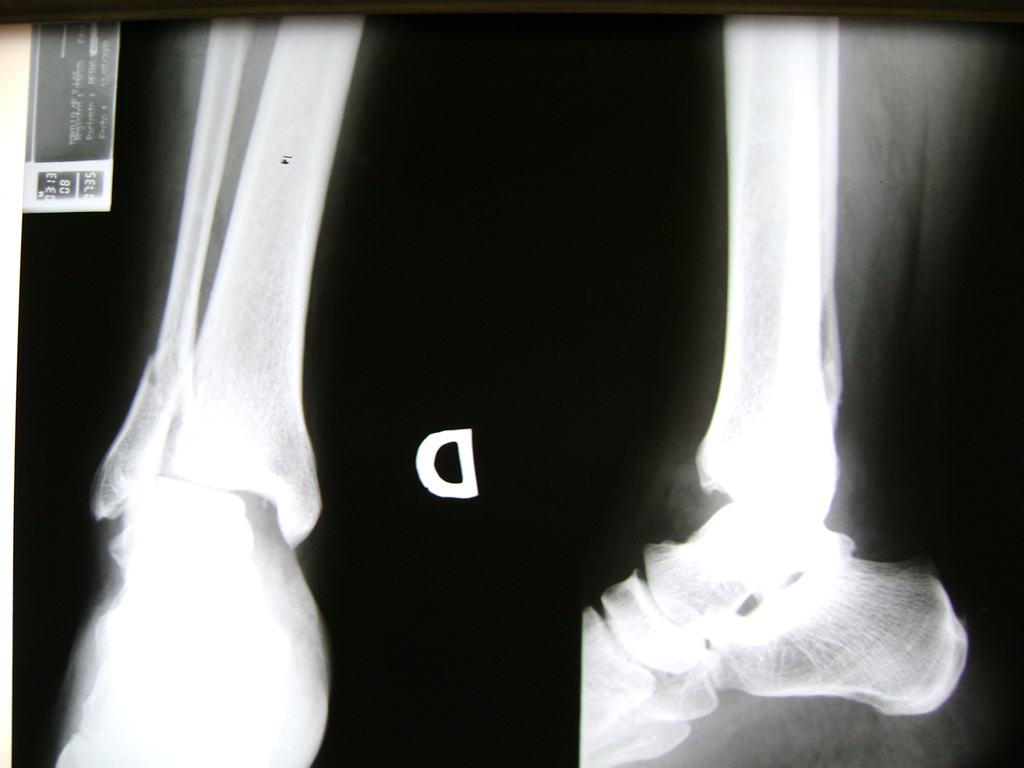

Una fractura de tobillo es la rotura de uno o más de los huesos del tobillo. Estas fracturas pueden ser:

Algunas fracturas de tobillo pueden requerir cirugía si:

- Los extremos de los huesos están desalineados entre sí (desplazados).

- La fractura se extiende hasta la articulación del tobillo (fractura intra-articular).

- Los tendones o ligamentos (tejidos que sujetan los músculos y los huesos entre sí) están rotos.

Cuando se necesita cirugía, es probable que esta implique el uso de clavijas de metal, tornillos o placas para sostener los huesos en su lugar mientras la fractura se consolida. Los elementos de soporte pueden ser temporales o permanentes.